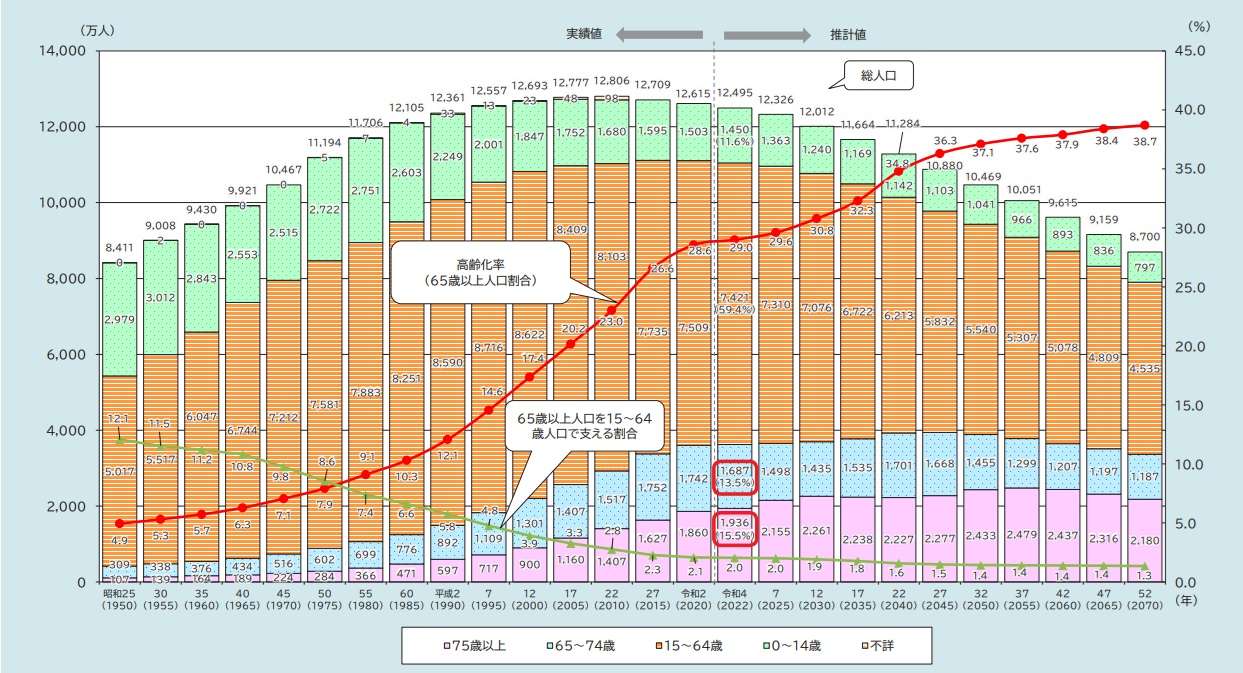

日本が直面している高齢化のスピードは、世界でも類を見ないものです。

長寿国として誇るべき成果である一方で、

医療・介護の負担、支える側の人口減少など、社会全体に大きな影響を与えています。

認知症予防が「個人の健康の問題」を超えて、社会的な課題として語られるのはこのためです。

■ 2025年、そして2040年へ —— 高齢者割合はますます増えていく

総務省のデータでは、2025年には65歳以上の高齢者が人口の約29.6%を占めると推計されています。

その後も高齢化は続き、生産年齢人口(15〜64歳)は加速度的に減少します。

つまり、

支える人が減り、支えられる人が増える構造が続く

ということです。

この人口構造の変化によって、医療・介護の現場はより多くの負担を抱えることになり、

認知症対策は“早めに取り組まなければ追い付かない課題”になってきています。